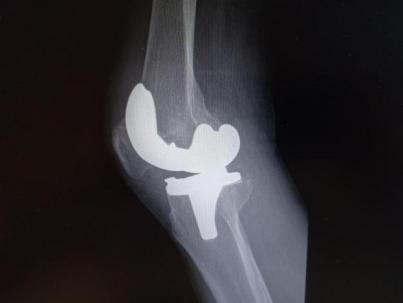

为提升区域内基层医疗机构糖尿病足诊疗服务能力、促进青年医师对糖尿病足的规范化诊治水平,遵义市第二城市医疗集团总院(贵州航天医院)圆满举办贵州省继续医学教育项目——胫骨横向骨搬移技术治疗糖尿病足专题研讨班。 贵州航天医院党委委员、副院长彭亮出席会议并致辞,遵义市第二城市医疗集团各成员单位,以及红花岗区、汇川区、绥阳县、桐梓县等多个区县的基层医疗机构骨干医师参加会议。 研讨班 本次研讨班以胫骨横向骨搬移技术在糖尿病足治疗中的应用为核心主题,围绕糖尿病药物治疗与生活方式管理策略、围手术期血糖精准调控要点、胫骨横向骨搬移技术典型病例深度解析、糖尿病足的临床分型与个体化治疗方案制定等临床实践中的热点与难点展开深入探讨,通过专题授课、案例研讨、互动交流等多元化形式,为参会者搭建了理论与实践结合的学习平台。 此次研讨班不仅为区域内基层医院搭建了学术交流与经验共享的平台,更对推动糖尿病足预防、诊断与治疗的规范化、系统化发展起到了积极作用,有效助力青年医师更新专业知识体系、提升临床技能,为进一步保障区域内糖尿病足患者的健康奠定了坚实基础。 贵州航天医院骨科专家简介 陈明勇 骨一科主任,副主任医师 临床擅长:从事创伤骨科工作约20年,对骨缺损、骨不连、骨肿瘤、肢体畸形等的肢体矫形重建及功能重建,慢性化脓性骨髓炎的根治治疗、糖尿病足的保肢治疗、快速康复理念(ERAS)下的老年骨折的诊治,四肢复杂骨折的诊治,四肢骨折等微创手术治疗具有丰富的临床经验。 2004年毕业于遵义医学院临床专业,曾在中国人民解放军总医院、广西医科大学第一附属医院、上海第六人民医院骨科进修。中国中西医结合学会骨伤科专业委员会横向骨搬移治疗糖尿病足及微血管网再生学组首届委员,遵义市医学会创伤分会常务委员。 瞿 晖 骨科党支部书记,骨二科主任,副主任医师 临床擅长:对骨科的常见病、关节外科、脊柱外科及运动医学疾病的诊治具有丰富的临床经验,熟练掌握骨科手术操作技术。 毕业于遵义医学院临床医学系,2005年前往广州中山大学第一附院骨显微医学部进修学习,2011年前往成都华西医院进修学习,并多次在省内外学习骨科相关知识,是中华医学会骨科分会会员。 赵小锋 中共党员,骨二科副主任,副主任医师 临床擅长:从事骨科临床工作11年,对骨科常见病、多发病诊疗有较为丰富的临床经验,擅长脊柱相关疾病诊断及治疗,尤其是颈、腰、腿疼痛疾病诊断及治疗,擅长胸腰椎骨折微创经皮穿刺内固定术、经皮穿刺椎体成形术、经皮穿刺脊柱内镜下腰椎间盘摘除术、单纯开创腰椎间盘摘除术、腰椎滑脱复位椎间植骨椎融合内固定术、腰椎管狭窄减压融合内固定术及人工髋、膝关节置换术等。 2012年毕业于遵义医学院外科学专业硕士研究生,2019年参加“遵义市115医学人才精英计划”于上海交通大学第一附属医院培训学习,2023年于北京大学第三人民医院脊柱外科进修学习,曾获得遵义市优秀医师荣誉称号。 遵义市手外科第一届委员,遵义市医学会创伤分会第一届委员,遵义市医学会创伤分会第二届委员,贵州省康复医学会第三届脊柱脊髓专业会委员,遵义市医学会烧伤与整形外科学分会委员,发表论文5篇,其中国家级核心期刊1篇,SCI论文1篇,主持市级课题1项并结题,参与市级课题2项。 赵兴东 骨科主任医师 临床擅长:擅长骨科的常见病及各种创伤、四肢骨折创伤修复、骨感染、手足疾病的诊治和手足体表畸形的矫形整复,熟练掌握骨科四肢骨病及创伤的手术操作技术,尤其在四肢关节复杂性损伤、手足外伤、组织缺损创面、难治创面的皮瓣修复方面及平足、高弓足矫形方面及四肢慢性疼痛诊治、康复方面具有丰富的临床经验。 硕士研究生,毕业于遵义医学院临床外科系,2015年前往山东省立医院手足外科进修学习;遵义市医学分会创伤分会第一、二届委员,遵义市手外科医学会第二委届员会常务委员;在省级及省级以上期刊发表文章9篇,参编著作2部,参与主持并完成市级课题1项,参与市级课题2项、省级课题1项。 张艳金 中共党员,骨科副主任医师 临床擅长:从事骨外科工作16年,对复合伤、多发伤的救治、四肢骨干骨折、关节周围骨折、骨肿瘤、骨髓炎等诊治具有丰富的临床经验。 中共党员,硕士研究生,2006年本科毕业于山西医科大学第二临床医学院,2011年研究生毕业于北京军区总医院;在“老年COPD患者合并髋部骨折的诊治”国际合作课题组研究两年,在老年髋部骨折的诊治方面具有丰富的经验,并发表论文6篇;主持遵义市级课题1项,承担遵义医科大学的临床教学工作,获得遵义医科大学优秀带教老师荣誉。编撰有《骨科疾病诊疗精粹》一书,开展2项新技术,编撰地方规范《务川自治县创伤骨科常见疾病诊疗规范》一书。 张俊凯 骨科副主任医师 临床擅长:从事骨科临床工作28年,对创伤骨折、骨感染、骨缺损、骨不连等外科诊治,四肢骨折的微创手术治疗,四肢复杂骨折(如关节内粉碎性骨折、多发骨折等)的损伤控制及手术治疗等具有丰富的临床经验。 1995年毕业于遵义医学院临床专业,2009年前往复旦大学附属医院骨科进修1年。 卢懿明 中共党员,骨科副主任医师 临床擅长:从事骨科工作18年,对创伤骨折、四肢骨折的微创手术治疗、四肢复杂骨折(如关节内粉碎性骨折、多发骨折等)的损伤控制及手术治疗,尤其是髋部骨折的PFNA等微创技术,踝关节骨折、膝关节周围骨折的Mipo微创技术等具有丰富的临床经验,开展了4项新技术,发明6项新型专利技术。 2005年毕业于遵义医学院临床专业,2017年,前往南方医科大学第三附属医院骨科进修半年,回院后运用Mipo技术对骨干骨折及干骺端骨折的治疗技术,同时积极开展骨盆骨折、髋臼骨折腹直肌外侧切口的应用;发表了多篇专业论文,经常参与省内外学术交流会授课,获得医院荣誉称号多个。 邬夏荣 骨科副主任医师 临床擅长:从事骨科工作16年,对四肢复杂骨折、骨肿瘤的诊治,尤其是足踝创伤、慢性踝关节损伤、平足症等诊疗具有丰富的临床经验。 2006年毕业于遵义医科大学临床医学专业,曾在陆军军医大学西南医院进修学习,发表多篇骨科学术论文。 余德怀 中共党员,骨科副主任医师 临床擅长:从事骨科工作10余年,对运动医学、骨关节、脊柱外科常见病、多发病的诊治具有丰富的临床经验。 硕士研究生,2011年毕业于遵义医学院临床医学专业,曾前往遵义医科大学附属医院运动医学专业进修学习;是贵州省医学会运动医学分会青年委员,西部关节镜联盟委员;发表多篇骨科学术论文。 冯 乾 骨科副主任医师 临床擅长:从事骨科工作近20年,熟练掌握骨科多发病及常见病的诊治,尤其对脊柱退变性疾病的诊断及治疗具有丰富的临床经验,主要研究脊柱微创相关治疗方式,能熟练开展椎间孔镜及UBE。 曾前往北京大学第三医院进修学习疼痛及椎间孔镜、首都医科大学友谊医院专业进修脊柱内镜;是贵州省康复医学会第三届脊柱脊髓专业委员会委员;发明专利3项、发表脊柱外科专业论文多篇。 贵州航天医院骨科简介 基本情况 贵州航天医院(原3417医院)骨科组建于1968年,前身是以创伤和断肢(断指)再植闻名于世的上海市第六人民医院骨科,中国断肢(断指)再植的奠基者、中科院院士陈仲伟等专家莅临科室指导医疗和教学,并在70年代开展了贵州省首例断肢(断指)再植手术。组建50余年来,诊治患者已逾百万,挽救了无数的伤病员,成为了保障遵义地区人民群众健康的重要支撑。 经过几代人的不懈努力,今天的骨科,已由创伤骨科发展至骨病、骨肿瘤、骨结核等领域,现有脊柱外科、关节外科、四肢创伤、手足外科四个亚专科,成为了集医疗、教学、科研于一体的综合学科,是贵州省临床重点专科、遵义市临床重点专科、遵义市骨科临床医学中心、遵义市基层骨科专科联盟理事长单位。 科室目前开放床位110张,共有医护人员50余人,副高级以上专家18人,硕士研究生15人。拥有一流骨科医疗设备多台,每年不定期选派优秀技术骨干到全国各大知名医学院校进修、学习、参观、交流,并邀请国内、国外知名专家教授来院进行交流、指导,通过不断引进国内外先进的诊疗技术,科室医疗技术水平稳步提升,为广大人民群众提供了优质的医疗服务。 专科特色 骨一科 (一)骨缺损、骨不连的肢体与功能重建 胫骨横向骨搬移技术治疗糖尿病足: (二)慢性骨髓炎的根治治疗 (三)肢体缺血性疾病如糖尿病足、脉管炎的保肢治疗 (四)皮瓣修复 (五)复杂创伤的治疗 (六)老年髋部骨折及小儿骨折快速手术 老年髋部骨折: 骨二科 (一)胸腰椎骨折微创经皮椎弓根螺钉固定术 (二)老年性骨质疏松性患者腰椎滑脱脊柱内固定术(骨水泥螺钉) (三)V形双通道脊柱内镜技术(VBE)腰椎融合术治疗腰椎退行性疾病 (四)老年性骨质疏松性骨折(PVP/PKP)术 (五)人工髋关节置换术 (六)双侧股骨头坏死人工全髋关节置换 (七)右侧全髋置换术后假体周围骨折翻修 (八)人工膝关节置换术 (九)人工膝关节假体松动翻修 (十)关节镜技术 传统手术切口 关节镜技术切口 诊疗范围 骨一科 1.四肢创伤、矫形。 2.手、足踝外科。 骨二科 End